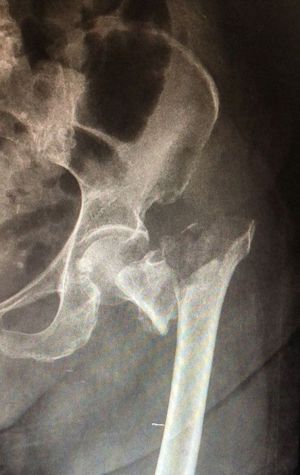

Fracture of the femur

Femur

R neck of femur fx

Neck of Femur Fracture